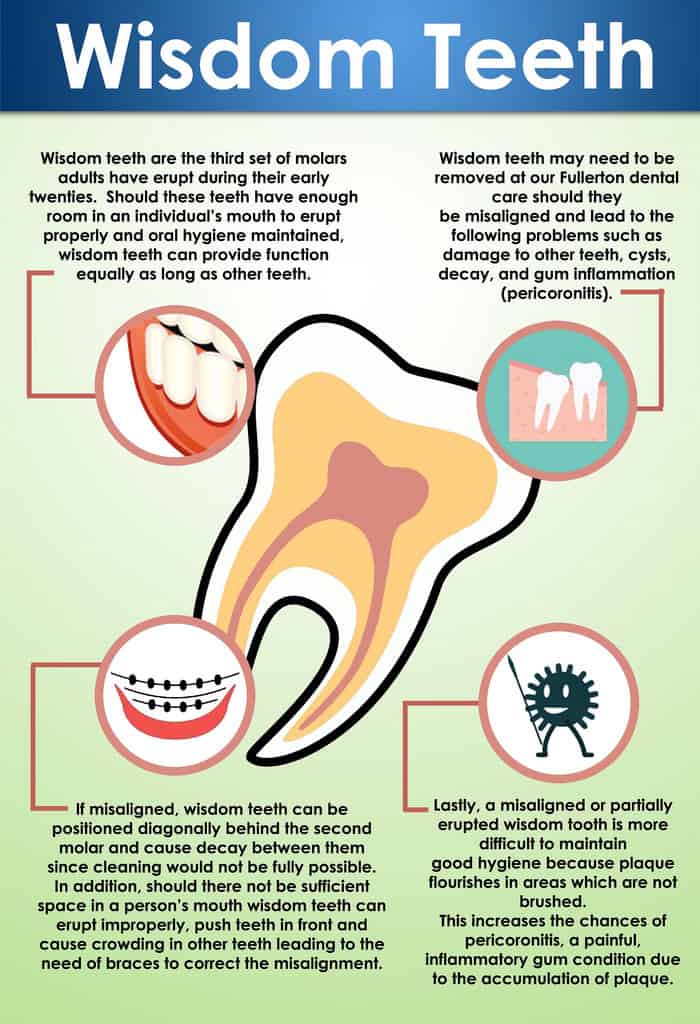

Tooth Extraction Aftercare Dental Infection Dental Extraction Wisdom

Wisdom Teeth Extractions Peach Smiles Lawrenceville GA

Good Wisdom Teeth